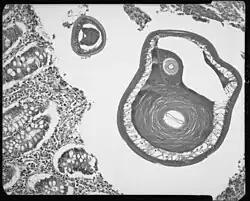

Trichuris, trouvé dans un appendice d'adulte.